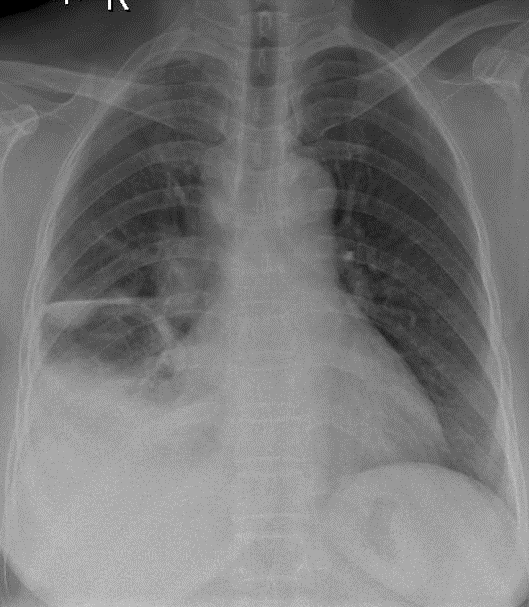

1-Tổn thương mờ đồng nhất thùy dưới phổi (P)=> Viêm phổi + đông đặc phổi 2-Tràn dịch màng phổi (P) 3-Nhiều cấu trúc dạng hạch vùng rốn phổi (P)